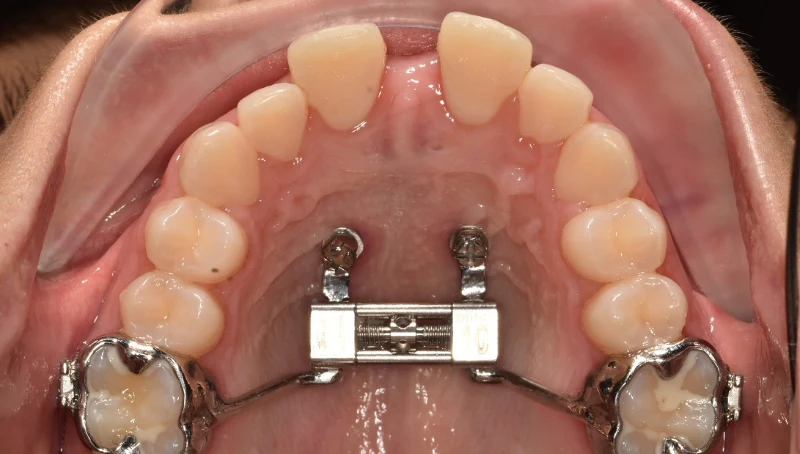

1754917002022.jpg 1515Кб, 3968x2976

3968x2976

Че будет завтра со мной?